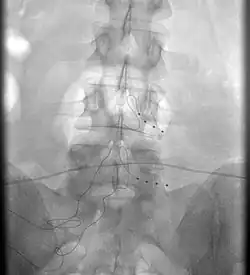

Die Implantation der Elektroden wird meist stationär durchgeführt. Eine oder mehrere Elektroden werden dabei im Epiduralraum eingesetzt, um dort die schmerzstillenden Impulse abgeben zu können. Erzeugt werden diese Impulse über einen üblicherweise im unteren Rücken oder im abdominalen Bereich, also in der Bauchregion, implantierten Impulsgenerator.

Die hochfrequente Rückenmarkstimulation arbeitet mit 10.000 Hz (= 10 kHz) außerhalb des Wahrnehmungsbereichs. Die Amplituden der Stromfrequenz liegen dabei sehr nahe beieinander und die anzuwendende Stromstärke ist sehr gering, sodass Kribbelparästhesien gar nicht erst entstehen. Die wirksame Lage der Elektroden lässt sich zuverlässig mittels einer Impedanzmessung, also einer elektrischen Widerstandsmessung, und einer Röntgen-Kontrolle in zwei Ebenen sicherstellen: Die Implantation kann dadurch in Vollnarkose erfolgen. Die Feineinstellung des Impulsgenerators erfolgt bei der hochfrequenten Therapie innerhalb der fachärztlichen Sprechstunde und unabhängig von den Aktivitäten des Patienten.